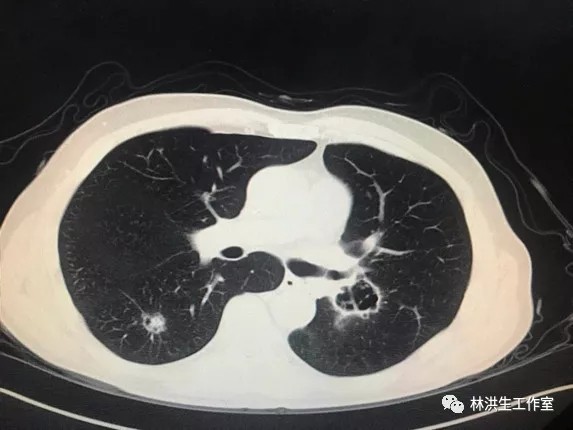

【诊断】左肺下叶腺癌术后双肺转移

【现病史】患者2014年7月就诊于中国医学科学院肿瘤医院诊断左肺下叶腺癌行手术切除pT3N2,术后辅助化疗后不到1年2015年5月复查发现双肺转移,基因检测阴性,中西医结合至今,病灶进展缓慢,体力状况PS 100分。

2017-06中药治疗前:双肺多发转移瘤继续较前增多、增大约1.9*2.3cm